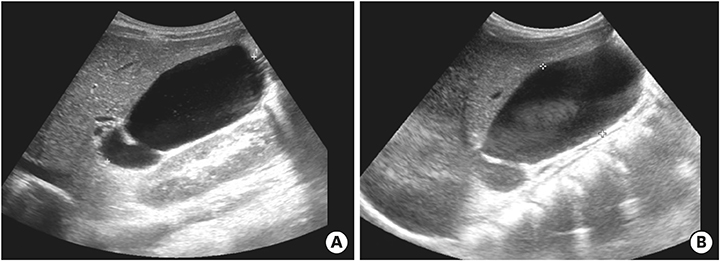

On the first day after admission, he received 2 g/kg IVIG and 50 mg/kg/day aspirin, following which his fever subsided and no further IVIG treatment was needed. His first echocardiography showed myocarditis (ejection fraction [EF], 45%) and mild ectasia of left main coronary artery (3.2–3.4 mm in diameter). On the second day after his admission, echocardiography (second follow-up) showed improved mild myocarditis (EF, 55%), improved ectasia of left main coronary artery (2.7–2.8 mm in diameter), and severe GB distension (8.9×4.6 cm in size), which possibly indicated GB hydrops (Fig. 2A). On the fourth day after his admission, although he had no fever and exhibited improvements in KD symptoms (i.e., eye injection, rash on abdomen, and cervical lymphadenopathy), he still complained of abdominal pain, distension, and tenderness of the RUQ. Follow-up laboratory findings were improved: neutrophilic leukocytosis (6,130 cells/mm3, with 33% neutrophils); decreased CRP (4.4 mg/dL), BNP (347 pg/mL), AST (40 U/L), and ALT (72 U/L); and improved hyperbilirubinemia (total bilirubin, 0.7 mg/dL). Echocardiography (third follow-up) showed normal completely improved carditis and still severe GB distension (10.2×5.5 cm in size) (Fig. 2B). Abdominal ultrasonography (US) was performed, which showed a markedly distended GB without stone, sludge, or wall thickening as well as normal bile ducts and liver morphology, which confirmed GB hydrops (Fig. 3A). On the sixth day after his admission, although his signs of KD had nearly disappeared, he still complained of abdominal discomfort, which had been moderately improving. The second follow-up abdominal US revealed a no notable change in GB distension compared to previous sonographic findings (Fig. 3B). An abdominal computed tomography (CT) scan was also obtained to exclude other hepatobiliary abnormalities, which showed similar findings as sonography, including a marked dilatation of the GB (8.0×5.5 cm in size) without stone, sludge, or wall thickening as well as normal bile ducts and liver morphology (Fig. 4). No complications necessitating surgical intervention had occurred and he was discharged 7 days after admission with only mild tenderness on the right upper-mid quadrant.

Abdominal ultrasonography showed severe gallbladder distension (A) 9.8×4.9 cm in size and (B) 9.3×4.3 cm in size.

Fig. 3 Abdominal ultrasonography showed severe gallbladder distension (A) 9.8×4.9 cm in size and (B) 9.3×4.3 cm in size.